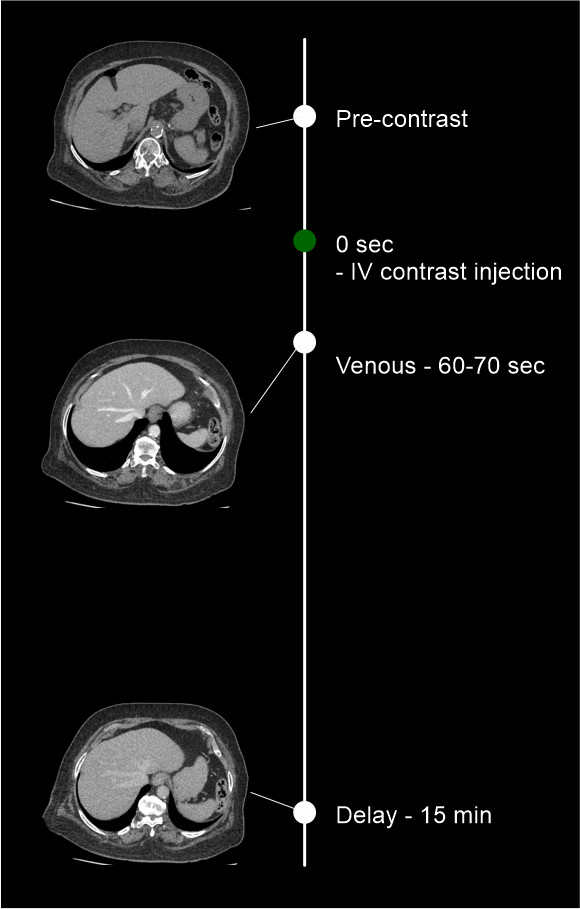

CT adrenal protocol helps to characterize masses in the adrenal glands. This study has multiple pre and post contrast phases that are used to identify contrast washout of masses.

Usually, there are three steps in the scan: pre-contrast, venous and delay.

- Set phase initiation using bolus timing method – refer multiphase contrast abdomen scan for more details.

A qualified Radiologist must calculate the Hounsfield unit (HU) values of adrenal lesions for all three phases to identify the contrast washout.